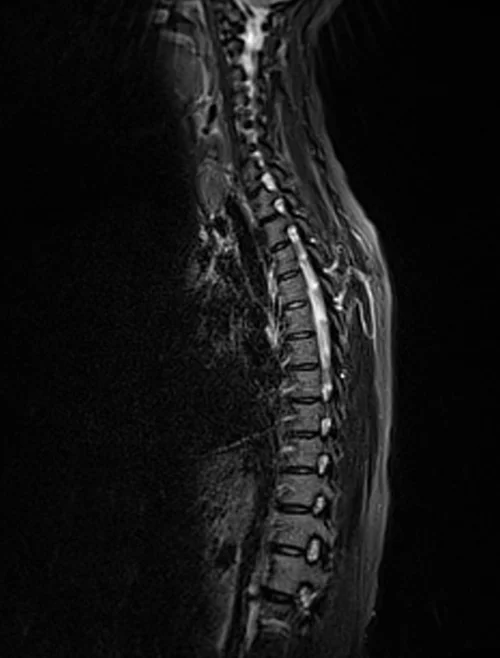

Thoracic spine mri sagittal stir images